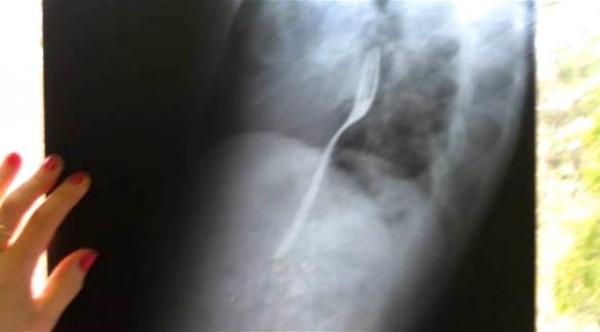

نقل شاب روماني إلى المستشفى في مدينة باكاو الرومانية بسبب معاناته من ألم شديد في معدته، فتبيّن في صورة الأشعة أنه ابتلع شوكة، بحسب موقع مترو البريطاني.

وكان رادو كالينسكو (25 عاماً) يشتكي من عدم الارتياح في معدته مع عدم إخبار الأطباء أنه ابتلع شوكة، إلى حين أصيبوا بالذهول عندما رأوا صور الأشعة، واكتشفوا جسماً غريباً استقر في بلعومه.